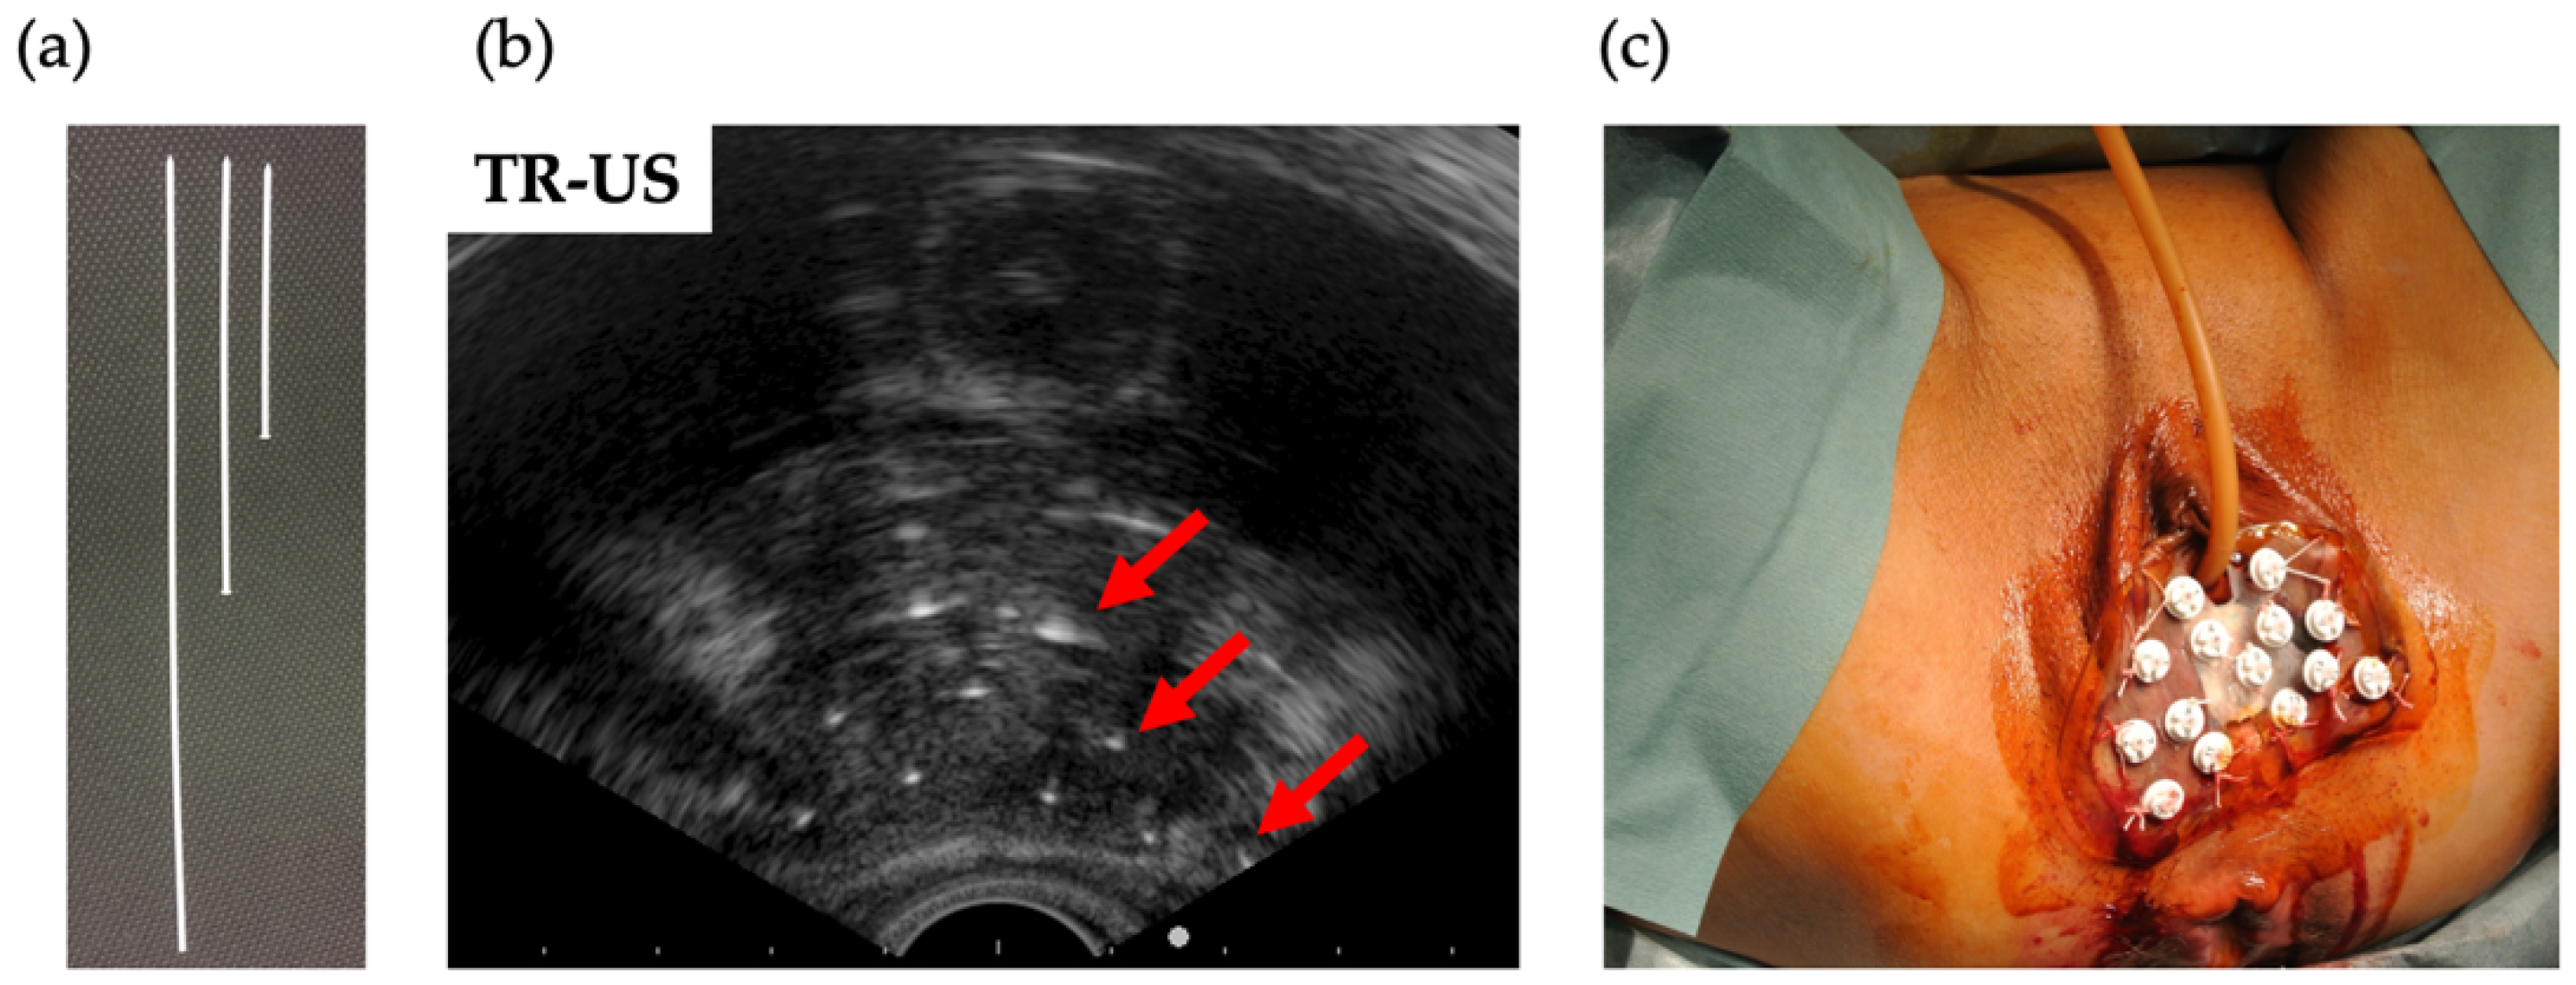

2.3. Interstitial Brachytherapy